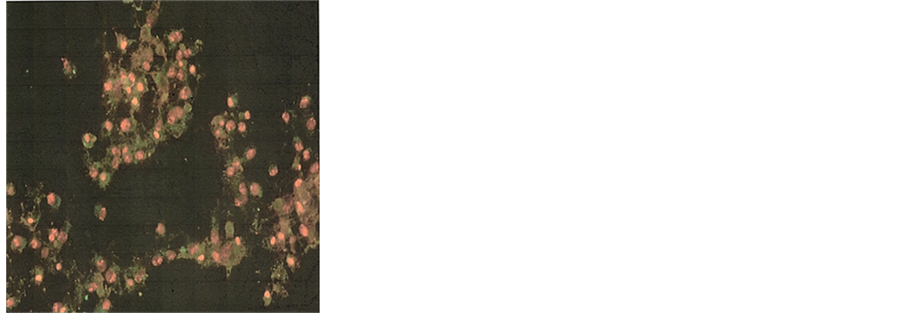

NM. Quantitative analysis of the data revealed the percentage of apoptotic cells to be 6% at 100 μg/ml (all in early phase apoptosis), 49% at 500 μg/ml (10% in early phase; 39% in late phase) and 83% for 1000 μg/ml NM (8% in early phase; 75% in late phase). It was observed that there was a corresponding decrease in percentage of live cells and an increase in percentage of cells in late apoptotic stages with increasing NM concentrations. A quantitative analysis of apoptosis induction in normal human dermal fibroblasts showed equivalency to DU-145 cells at 100 μg/ml. However, at higher concentrations of NM the induction of apoptosis was significantly lower in NHDF cells as compared to DU-145 cells. The percentage of apoptotic NHDF cells was 7% at 100 μg/ml (2% in early phase, 5% in late phase), 25.6% at 500 μg/ml (4.6% in early phase, 21% in late phase) and 76.5% at 1000 μg/ml (23.5% in early phase, 53% in late phase). Photomicrographs of apoptotic DU-145 cells and NHDF are shown in Figures 2(a)-(d) and Figures 3(a)-(d), respectively. The quantitative analysis of live, early and late DU-145 prostate cancer cells and NHDF cells are shown in Figure 2(e) and Figure 3(e), respectively.

Figure 3. Effect of NM on induction of apoptosis in normal NHDF cells. Photomicrographs of NHDF cells (×20 magnification) treated with (a) 0 mg/ml, (b) 100 mg/ml, (c) 500 mg/ml, (d) 1000 mg/ml concentrations of NM respectively. (e) Analytical representation of the differential distribution of cells in early or late phases of apoptosis upon treatment with 0, 100, 500 and 1000 mg/ml NM concentrations.

NHDF cells treated with increasing concentrations of NM. While the percentage of apoptotic cells was 7% at 100 μg/ml, it increased to 25.6% at 500 μg/ml and to 76.5% at 1000 μg/ml NM.